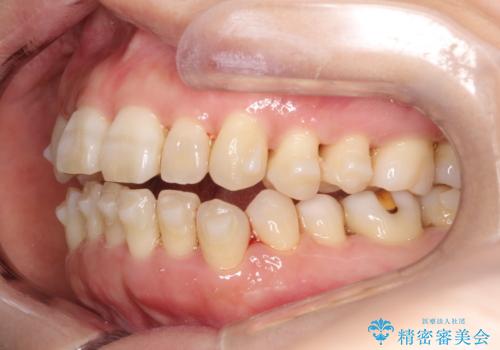

- 上下の前歯の開き(開咬)と上下前歯にガタつき(叢生)が見られます。

マウスピース矯正ではメカニクス的に開咬へのアプローチが容易です。

インビザラインの特色を生かした歯牙移動計画を作成し、非抜歯にて治療を行いました。